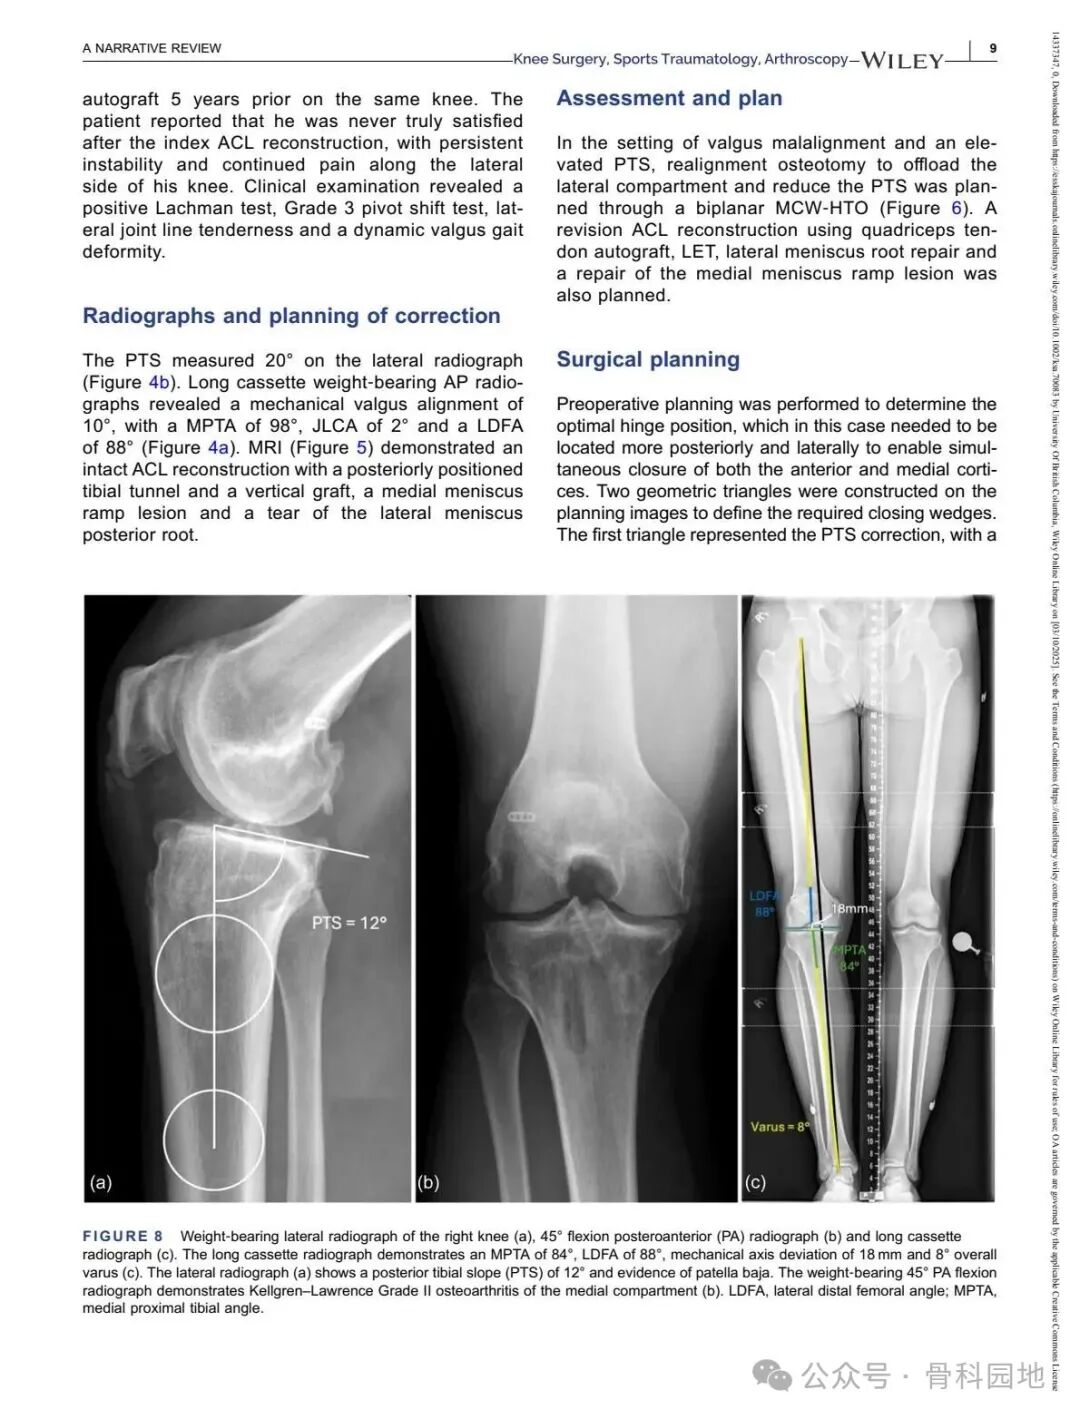

Although conventional high tibial osteotomy (HTO) primarily addresses coronal plane malalignment, the importance of sagittal plane alignment—specifically the posterior tibial slope (PTS)—cannot be overlooked in the setting of cruciate ligament insufficiency. Combined coronal and sagittal plane deformities are relatively rare and present unique surgical challenges. This narrative review summarizes the available literature and presents technical tips for managing complex biplanar deformities through a case‑based discussion of different techniques.